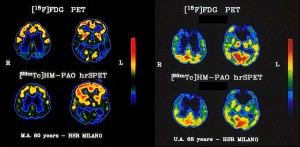

Immagini tomografiche PET (metabolismo di glucosio) e SPECT (perfusione) a due diversi livelli in un paziente affetto da malattia di Alzheimer (sinistra) e in un paziente con demenza frontotemporale (destra)